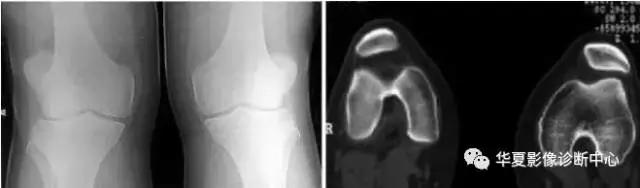

5分裂 (二分)髌骨

常见于儿童,多双侧性。 一般认为是正常骨化的变异,可在十几岁时融合。

症状:运动时疼痛或运动后疼痛,膝关节屈曲时疼痛、下跪时疼痛,上下楼梯时疼痛,行走时疼痛,受冷时疼痛。

分裂部扣击痛:可诱发有症状的分裂髌骨的疼痛,无症状者阴性。分裂骨片局部骨性隆起。 股四头肌萎缩, 髌骨摩擦音,大多无关节积液、跛行和关节活动度受限。有时需与骨折鉴别。